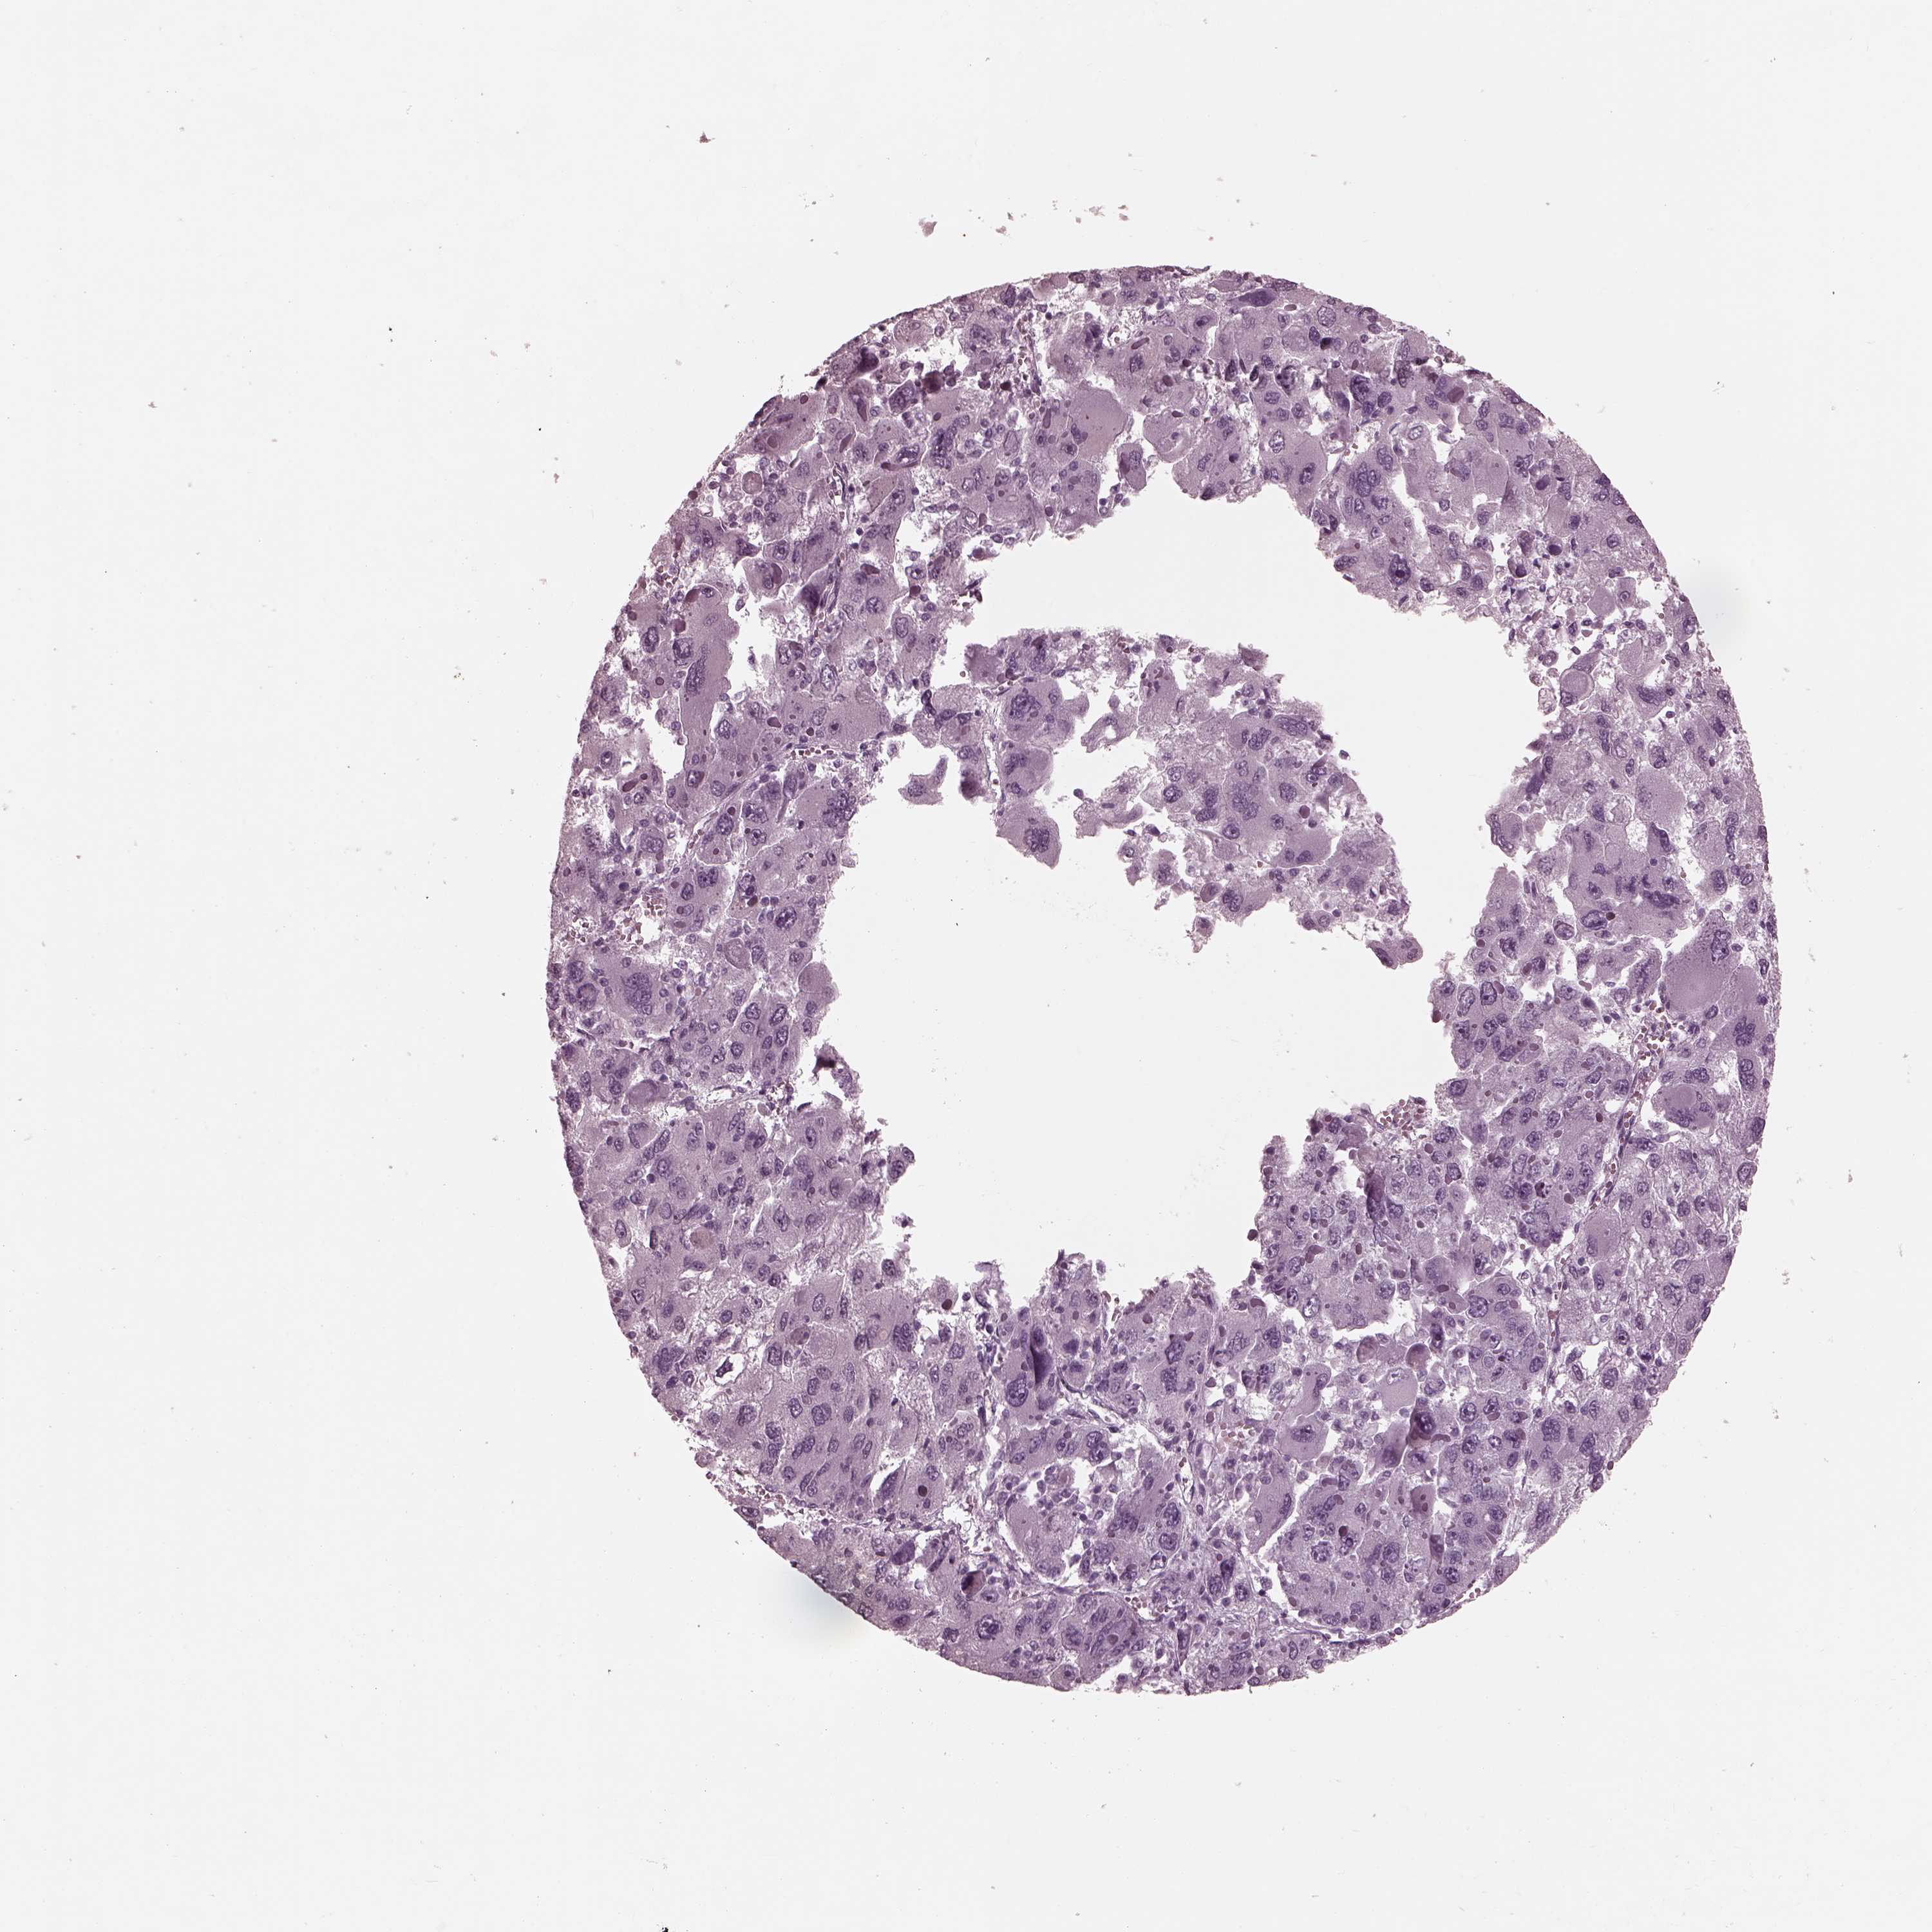

LIVER CANCER - Protein expressioni

A mouse-over function shows sample information and annotation data. Click on an image to view it in a full screen mode. Samples can be filtered based on level of antibody staining by selecting one or several of the following categories: high, medium, low and not detected. The assay and annotation is described here.

Note that samples used for immunohistochemistry by the Human Protein Atlas do not correspond to samples in the TCGA dataset.

Antibody stainingi

Antibody staining in the annotated cell types in the current human tissue is reported as not detected, low, medium, or high, based on conventional immunohistochemistry profiling in selected tissues. This score is based on the combination of the staining intensity and fraction of stained cells.

Each image is clickable and will lead to virtual microscopy that enables deeper exploration of all samples and also displays staining intensity scores, fraction scores and subcellular localization as well as patient and tissue information for each sample.

Antibody HPA038811

Staining

High

Medium

Low

Not detected

Intensity

Strong

Moderate

Weak

Negative

Quantity

>75%

75%-25%

<25%

None

Location

Nuclear

Cytoplasmic/membranous

Cytoplasmic/membranous,nuclear

Carcinoma, Hepatocellular, NOS